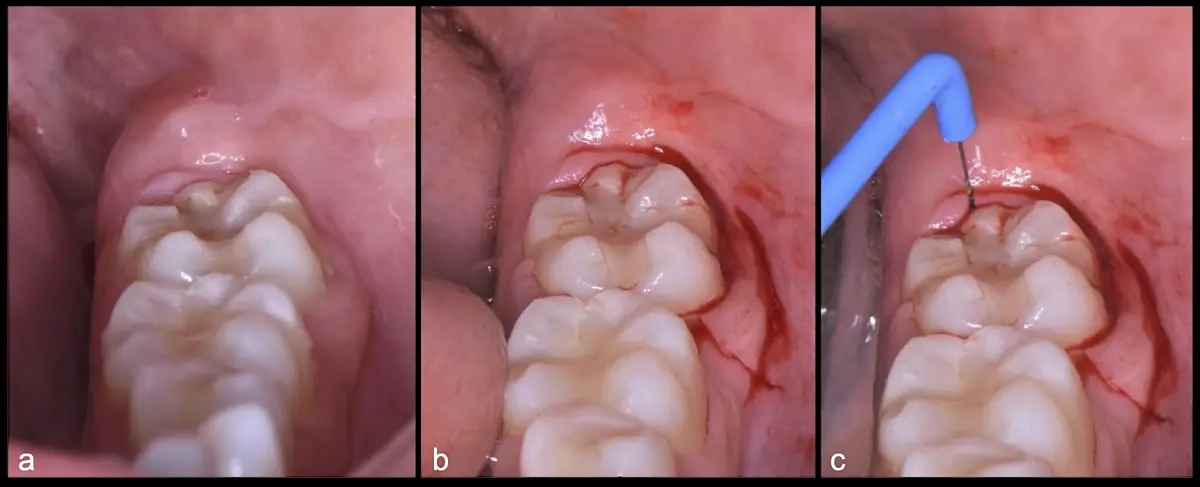

Es imprescindible conocer la ubicación de la tercera molar. Se puede emplear, adicionalmente a la evaluación clínica, herramientas radiográficas (panorámica y periapical) y tomográficas (Cone beam) para determinar la posición, grado de retención y proximidad a estructuras vecinas de riesgo como el nervio dentario inferior y así evitar lesiones (Figura 1).

El procedimiento se inicia colocando anestesia troncular para bloqueo del nervio dentario inferior y sus ramas. Luego, se establecerá el diseño de acceso según la disposición de la molar a extraer. Para fines didácticos, se explicará cómo se realizaría la extracción de la molar de la Figura 1: se realiza una incisión horizontal a nivel de la zona retromolar hasta llegar a distal de la segunda molar, continuándose con una incisión intrasurcular hasta mesial de la segunda molar, finalizando con una incisión vertical a espesor total hasta llegar a la línea mucogingival (Figura 2).